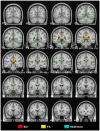

Methods: The biomarker question was addressed in this study by adopting a standardised protocol both for the whole brain (tract-based spatial statistics), and for a region of interest: the midline corpus callosum. In order to study the evolution of tensor changes, cross-sectional data from very mild (N = 21) and mild (N = 22) Alzheimer's disease patients were examined as well as a longitudinal cohort (N = 16) that had been rescanned at 12 months.

Findings and significance: The results revealed that increased axial and mean diffusivity are the first abnormalities to occur and that the first region to develop such significant differences was mesial parietal/splenial white matter; these metrics, however, remained relatively static with advancing disease indicating they are suitable as 'state-specific' markers. In contrast, increased radial diffusivity, and therefore decreased fractional anisotropy-though less detectable early-became increasingly abnormal with disease progression, and, in the splenium of the corpus callosum, correlated significantly with dementia severity; these metrics therefore appear 'stage-specific' and would be ideal for monitoring disease progression. In addition, the cross-sectional and longitudinal analyses showed that the progressive abnormalities in radial diffusivity and fractional anisotropy always occurred in areas that had first shown an increase in axial and mean diffusivity. Given that the former two metrics correlate with dementia severity, but the latter two did not, it would appear that increased axial diffusivity represents an upstream event that precedes neuronal loss.